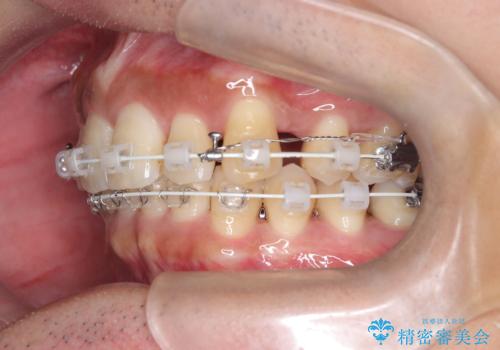

- 前歯のデコボコ(叢生)と、上下の歯の重なりが深い「ディープバイト(過蓋咬合)」を主訴にご来院されました。精密検査の結果、歯が並ぶスペースが不足しているため、上顎左右の小臼歯を抜歯することでスペースを確保し、全体の咬み合わせを改善する治療計画を立案しました。これにより、見た目の改善だけでなく、過度な咬み合わせによって生じる歯や顎への負担も軽減することを目指します。

今回の矯正治療では、まず歯が並ぶスペースを確保するため、上顎の小臼歯を抜歯しました。抜歯によってできたスペースを利用して前歯を奥へ移動させ、デコボコを解消。同時に、奥歯の咬み合わせを調整することで、深すぎた咬み合わせであるディープバイトも改善しました。治療の結果、長年気にされていた前歯のデコボコが解消され、理想的な歯並びに。さらに、正しい咬み合わせを獲得したことで、機能的にも安定した美しい口元になりました。